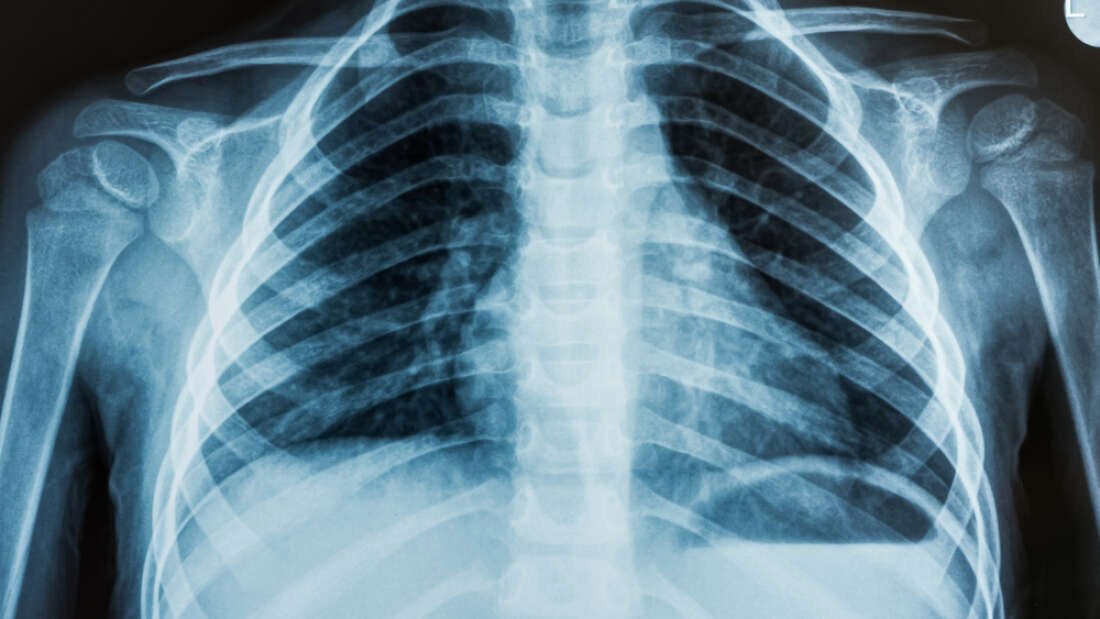

Bir doktor, sadece röntgen görüntülerine bakarak hastanın siyahi mi, Asyalı mı, yoksa beyaz mı olduğunu ayırt edemez. Massachusetts Teknoloji Enstitüsü ve Harvard Tıp Okulu'ndaki araştırmacıları da içeren uluslararası bir ekibin The Lancet Digital Health tıp dergisinde yayınladığı şaşırtıcı bir makaleye göre bir bilgisayar bunu yapabiliyor olabilir![2]

Çalışma, X-ışınlarını ve CT taramalarını okumak için eğitilmiş bir yapay zeka programının, bir kişinin ırkını %90 doğrulukla tahmin edebileceğini buldu. Ancak çalışmayı yürüten bilim insanları, bilgisayarın bunu nasıl çözdüğüne dair hiçbir fikirleri olmadığını söylüyorlar. MIT Elektrik Mühendisliği ve Bilgisayar Bilimi yardımcı doçenti ve makalenin ortak yazarı Marzyeh Ghassemi şöyle diyor:

Amerika Birleşik Devletleri, Kanada, Avustralya ve Tayvan'dan bilim insanlarını içeren araştırma ekibi, ilk olarak, her görüntünün kişinin ırkıyla etiketlendiği standart X-ışınları ve CT taramaları veri setlerini kullanarak bir yapay zeka sistemi eğitti. Görüntüler, göğüs, el ve omurga dahil olmak üzere vücudun farklı bölgelerinden geldi. Bilgisayar tarafından incelenen tanı görüntüleri, ten rengi veya saç dokusu gibi belirgin bir ırk belirteçlerini içermiyordu.

Yazılıma çok sayıda ırk etiketli görüntü gösterildikten sonra, henüz etiketlenmemiş farklı görüntü kümeleri de gösterildi. Program, görüntülerdeki insanların ırkını, ortalamada %90'ın oldukça üzerinde, yani dikkate değer bir doğrulukla tespit edebildi. Aynı boy, yaş veya cinsiyetteki insanlardan alınan görüntüler analiz edildiğinde bile, yapay zeka, siyahi ve beyaz hastaları doğru bir şekilde ayırt etti. Ama nasıl?